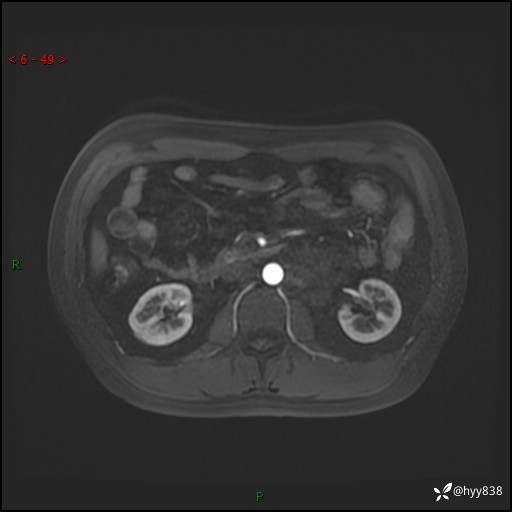

现病史:患者3月余前检查发现左侧腹膜后占位,大小约3.7*4.9cm,平素无腰疼,无肉眼血尿,无尿频尿急等不适,当时未特殊处理,在门诊复查CT提示左侧腹膜后占位,门诊拟“左侧腹膜后占位”收入院。 起病以来,患者精神佳,饮食、睡眠良好,大小便正常,体力体重无明显变化。

MRI增强